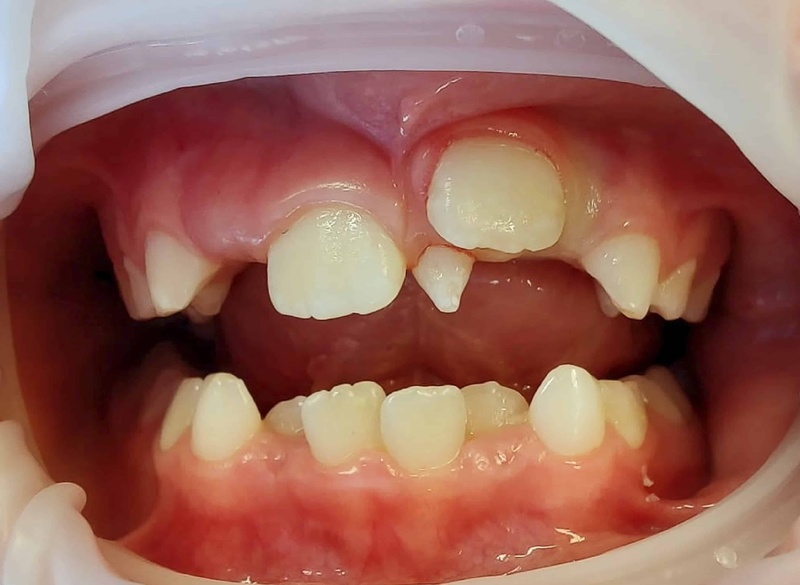

- Răng mọc không đúng vị trí: Đây là dấu hiệu dễ thấy nhất. Bạn có thể thấy một chiếc răng mọc chen vào giữa hai răng cửa (gọi là Mesiodens), mọc lệch hẳn ra ngoài hoặc vào trong cung hàm (răng khểnh, răng mọc lẫy).

- Chậm mọc răng vĩnh viễn: Đây là dấu hiệu quan trọng ở trẻ em. Răng thừa đặc biệt là răng ngầm có thể cản đường, khiến răng vĩnh viễn (nhất là răng cửa) mọc lên rất muộn hoặc không mọc được.

- Răng mọc chen chúc, xô lệch: Sự xuất hiện của răng thừa chiếm mất không gian, khiến các răng vĩnh viễn khác không đủ chỗ, dẫn đến mọc chen chúc, xoay trục.

- Khe thưa lớn bất thường: Đôi khi, một răng thừa mọc ngầm giữa hai răng cửa có thể đẩy chân răng của chúng ra xa nhau, tạo ra một khe thưa lớn.

- Chậm mọc răng: Răng thừa là nguyên nhân phổ biến nhất gây chậm mọc hoặc mọc lệch lạc của răng vĩnh viễn. Tình trạng này đặc biệt hay gặp ở răng cửa hàm trên/ dưới của trẻ em.